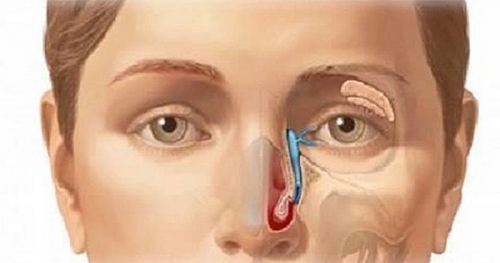

Ung thư xoang mặt: Dấu hiệu nhận biết và nguyên nhân gây bệnh

Bài viết này sẽ cung cấp cho bạn những thông tin hữu ích về bệnh ung thư xoang mặt như: khái niệm, triệu chứng biểu hiện, nguyên nhân gây bệnh...